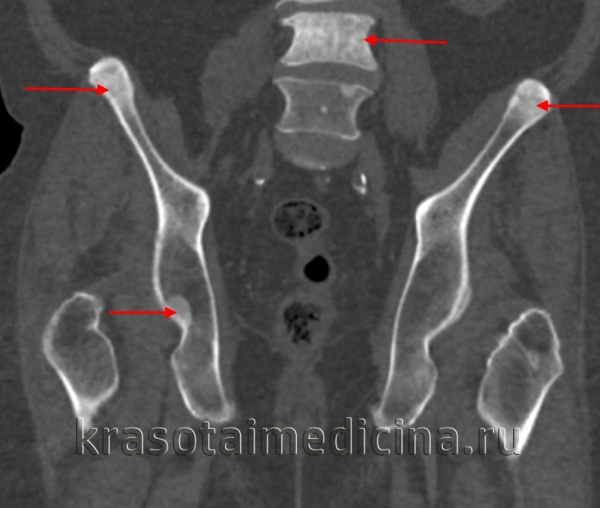

- Рисунок по типу «кость в кости»:

Наиболее очевиден в позвоночнике

Этот признак выявляется и в подвздошной кости

Как и недостаточная тубуляция, признак «кость в кости» проявляется при невозможности ремоделирования кости

По мере роста кортикальный слой кости не подвергается резорбции и визуализируется внутри более крупной (более взрослой) кости

Мужчины и женщины болеют одинаково часто. На основании рентгенологических данных выделяют два типа аутосомно-доминантного остеопетроза. Для I типа характерно утолщение свода черепа, в то время как при II типе обнаруживают «полосатый» позвоночник, дугообразные участки остеосклероза в крыльях подвздошных костей («кость в кости») и уплотнение губчатого вещества костей. При обоих типах уменьшаются костномозговые полости.

о Эндокости - «кость в кости» (нерезорбировавшиеся центры первичной оссификации)

Кость в кости» (нерезорбировавшиеся центры первичной оссификации)